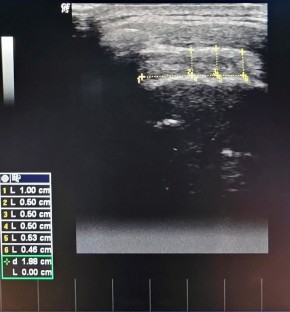

Fig. 1

Fig. 2

Fig. 3

Fig. 4

Fig. 5